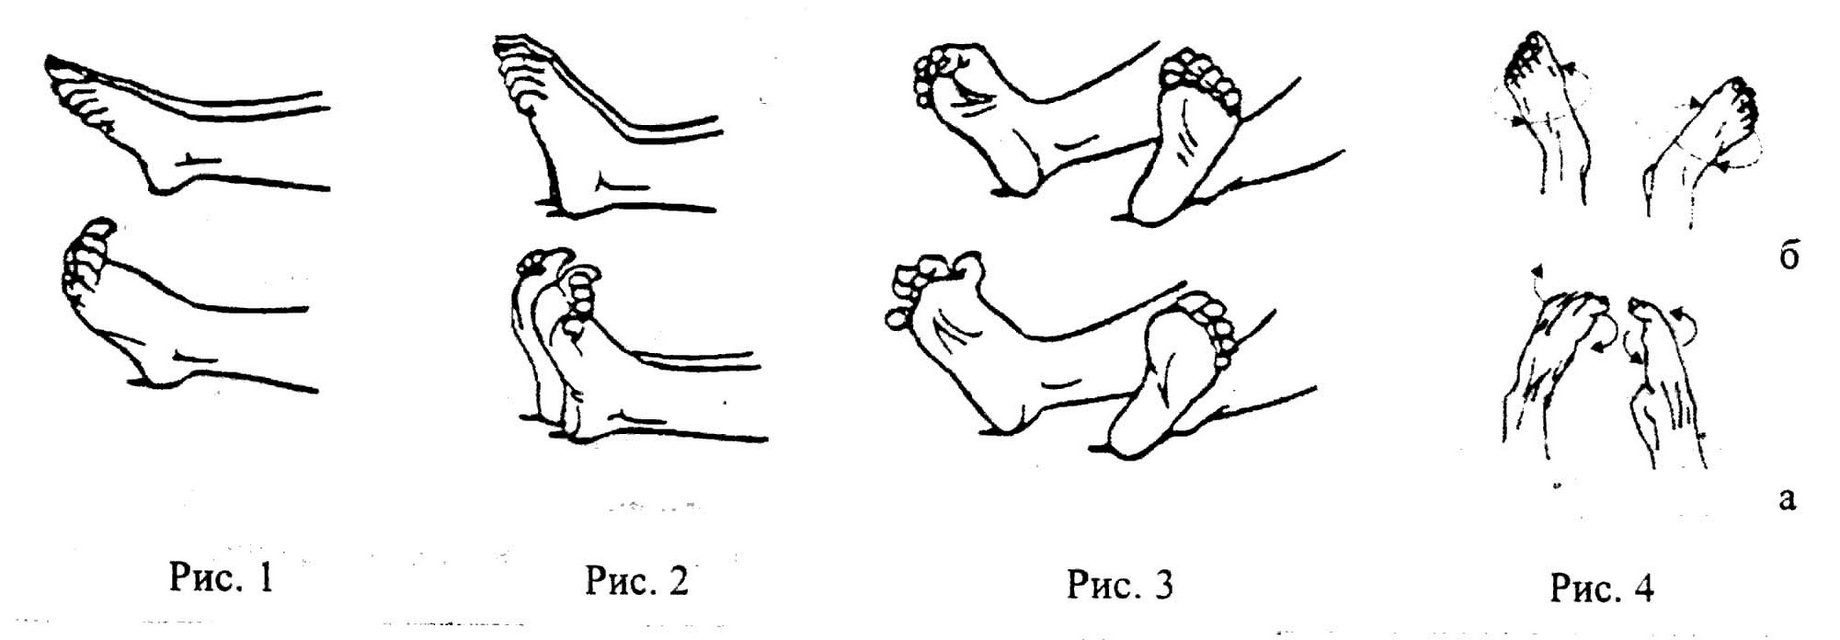

Артроз голеностопного сустава 2 степени схема лечения